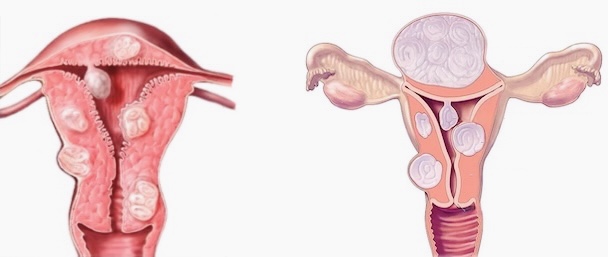

- Patologías ginecológicas frecuentes como quistes ováricos, endometriosis y miomas.

- Cirugías ginecológicas ambulatorias (ej. extirpación de quistes, miomas, lesiones benignas).

Un leve malestar es común, pero si el dolor es incapacitante, podría ser señal de endometriosis u otra afección que requiere atención médica.